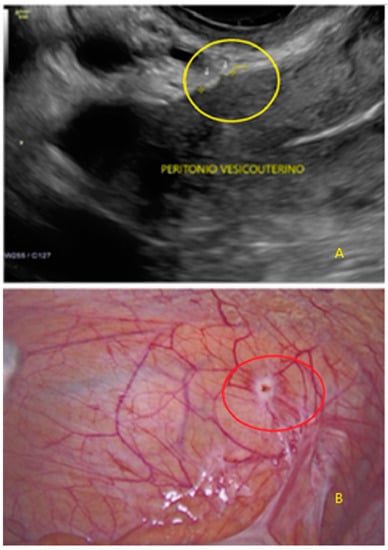

- The lesion may be convex, protruding from the peritoneal surface into the peritoneal cavity (we called this “bulging”), or it may appear as a concave defect in the peritoneum (we called this a “pocket”).